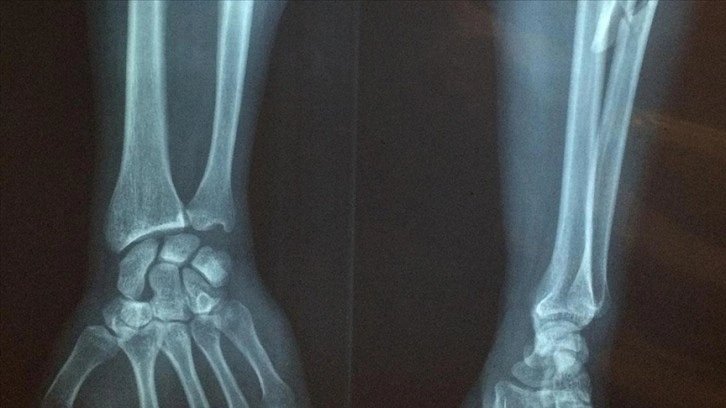

Lapçın, röntgende görülmeyen stres kırığının tespiti için farklı bir görüntüleme yapılması gerektiğine dikkati çekerek, "Bu da MR oluyor. Çünkü MR, kemiğin içerisindeki sıvı düzeyini, ödemi çok rahatlıkla gösterdiği için röntgenin yakalayamayacağı bu süreci çok rahatlıkla yakalıyoruz." bilgisini verdi.